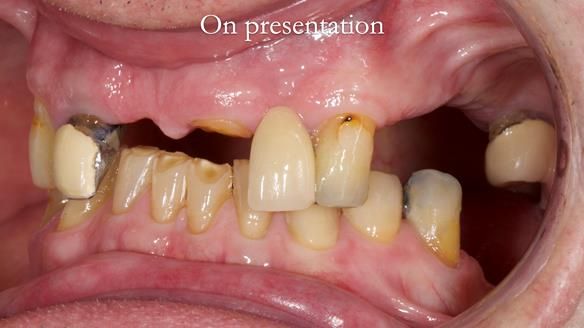

This edition features the case of Edgar, who sought help for a poorly fitting, acrylic-based partial denture that rocked, affected his speech, and caused discomfort. After considering various treatment options, including dental implants, Edgar opted for a metal-based removable partial denture, designed by myself with input from my technician, Rowan Garstang.

Treatment Process: I provided the clinical work while Rowan Garstang delivered the technical aspects. The treatment required fifteen visits to fit and review Edgar.